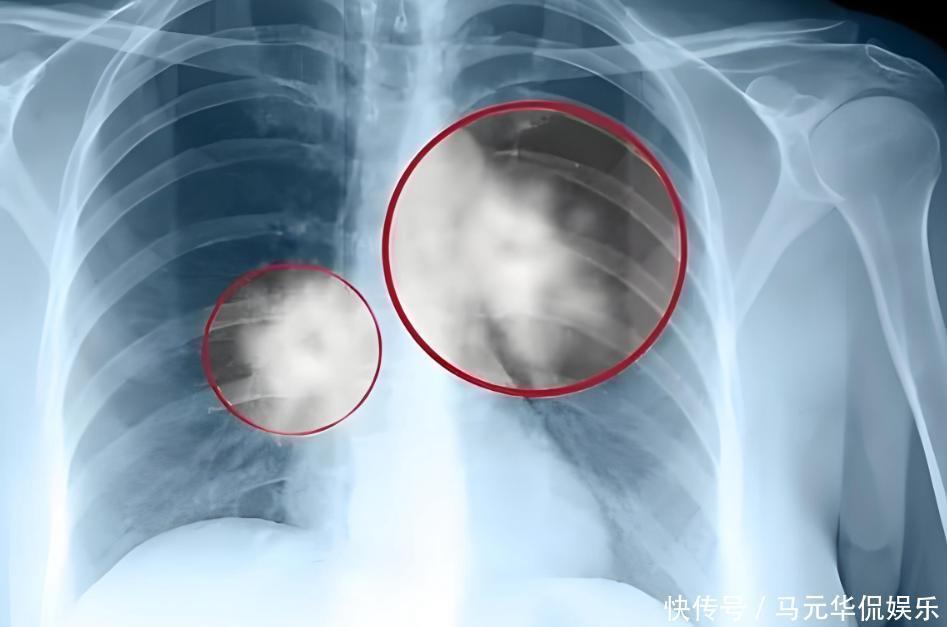

即便三四年前发现肺部结节,医生的警告他也没放在心上。甚至自嘲魔术师肺里有点雾很正常。更让人揪心的是,他的家族有着肺癌遗传史。

他的叔叔就因肺癌离世,双重风险下,他依旧没能戒掉烟瘾。2024年春节前夕,刘谦在体检中被查出肺部有大片阴影。进一步检查后,“肺腺癌”的诊断结果如同晴天霹雳砸在他头上。